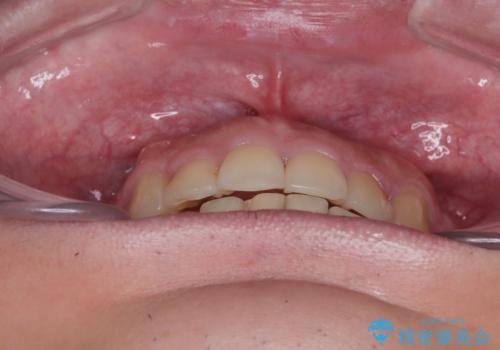

右上第一小臼歯は歯根癒着により移動せず、左上第二小臼歯は移動はするものの非常に動きが鈍かったため、抜歯したスペースを閉じるまでに非常に時間がかかってしまいました。

患者様には辛抱強く治療にお付き合いいただき、すっきりとした口元に仕上げることができました。